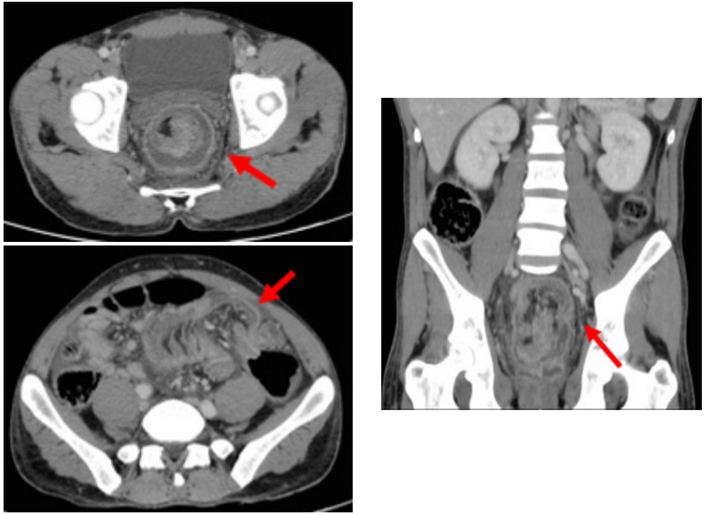

Varón de 39 años, natural de Marruecos, sin antecedentes de interés, que acude a urgencias por cuadro clínico de 15 días de dolor abdominal, asociado a vómitos intermitentes, deposiciones diarreicas y rectorragia, con empeoramiento progresivo hasta presentar obstrucción intestinal de 48 horas de evolución. La radiografía abdominal mostró dilatación marcada del colon (figura 1), que se corroboró con la TC abdominal (figura 2), donde además se visualizó una extensa invaginación a nivel del colon sigmoides, sin clara lesión subyacente, condicionando una oclusión mecánica con distensión retrógrada (ciego de 8 cm de diámetro con válvula competente). No se identificaron neumoperitoneo ni otros signos de perforación.

Se realizó colonoscopia observándose una lesión como cabeza de invaginación sugestiva de pólipo, que por su gran tamaño impidió la reducción endoscópica con éxito. Se indicó por tanto cirugía urgente, realizándose laparotomía media, hallando un segmento de unos 30 cm de invaginación a nivel del sigmoide, con inadecuada perfusión en este segmento de colon. Se practicó sigmoidectomía más anastomosis colorrectal termino-terminal con endograpadora circular de 29 mm.

El paciente presentó buena evolución postoperatoria, con íleo paralítico resuelto con manejo conservador, por lo que se dio de alta a los 6 días. En la anatomía patológica se confirmó la presencia en el intussusceptum de un adenoma tubular con displasia de bajo grado (figura 3). En consulta de control al mes, el paciente está asintomático. Actualmente en seguimiento ambulatorio, no ha presentado recidiva de la enfermedad.